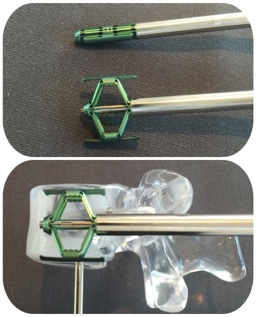

La vertebroplastia consiste en rellenar el cuerpo vertebral con cemento directamente a través de los trócares (Fig 1 y Fig 2).

La cifoplastia es lo mismo, pero con un paso previo, consistente en generar un hueco o cavidad dentro de la vértebra fracturada. Este hueco se hace con un balón, globo o dispositivo (similar al gato para levantar un coche con la rueda pinchada), que una vez dentro de la vértebra, se hinchará o expandirá para tratar de levantar la vértebra aplastada o generar dicho hueco, que posteriormente albergará el cemento (Fig 3).